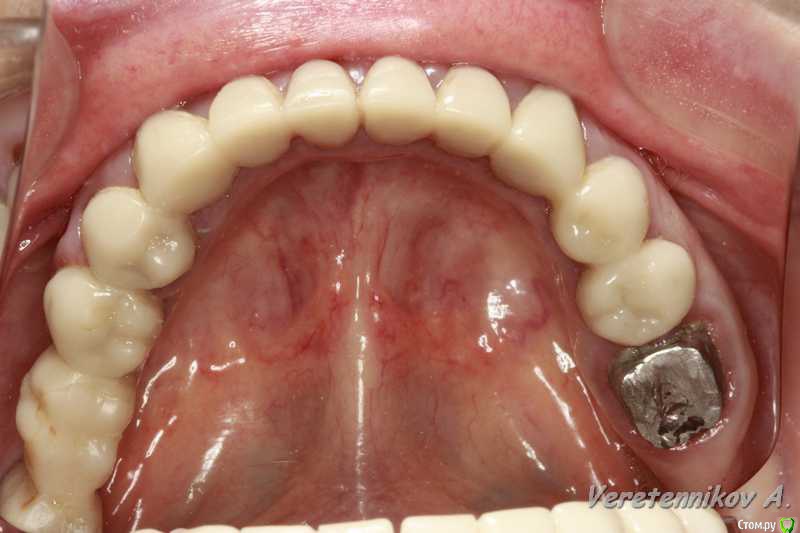

an_ver Опубликовано 1 мая, 2015 Поделиться Опубликовано 1 мая, 2015 (изменено) Обратилась пациентка, ходит с временными уже 1-1,5..что то шлифовали, что то меняли...не может привыкнуть((. Из того что увидел...гиперемия слизистой десны, слегда синюшность,сосочки раздавлены,акриловые временные (Синма) наверное.Сделали орто..и опа! Шедевр бюджета! Все ПУЛЬПИРОВАЛИ, впердолили вкладки и больше всего убила пластина....сеогодня придет...сфотаю выложу...надо как то девушке помочь. Изменено 1 мая, 2015 пользователем an_ver Ссылка на комментарий

M@estro Опубликовано 1 мая, 2015 Поделиться Опубликовано 1 мая, 2015 Времяши на формиках. Уступы километр .. Печаль. Фото кидай и модели Ссылка на комментарий

an_ver Опубликовано 1 мая, 2015 Автор Поделиться Опубликовано 1 мая, 2015 Времяши на формиках. Уступы километр .. Печаль. Фото кидай и моделиДа уж...моделей еще нет.Сегодня только фото будет.Прилегание фкладок и направление ножек вкладок совсем в ступор ввели...блин как можно мимо захренячить...иного слова нет....ну и запил...думаю пипец там Ссылка на комментарий

kriokov Опубликовано 1 мая, 2015 Поделиться Опубликовано 1 мая, 2015 запил дебильный. Надо смотреть фотки, может за счет хирургического удлинения коронковой части выйти из положения можно , если глубоко под десну не сгнило. Пародонтита то нет. Судя по всему рукотворные там проблемы с десной .Пластина сстоит как вкопанная? Ссылка на комментарий

an_ver Опубликовано 2 мая, 2015 Автор Поделиться Опубликовано 2 мая, 2015 Вот фото Ссылка на комментарий

M@estro Опубликовано 3 мая, 2015 Поделиться Опубликовано 3 мая, 2015 (изменено) Десневая ) Только и удлинняйся ) Главное - достать аккуратно. На этапы разбивай работу, пусть с временными походит. Медленно , планомерно - все будет. P.s. Если пациентка неспособна / не готова оценить работу - браться не стоит, имхо. Это не одиночку поставить и забыть. Изменено 3 мая, 2015 пользователем M@estro 2 Ссылка на комментарий